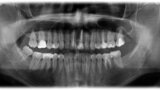

Leczenie endodontyczne autogennego przeszczepu zęba